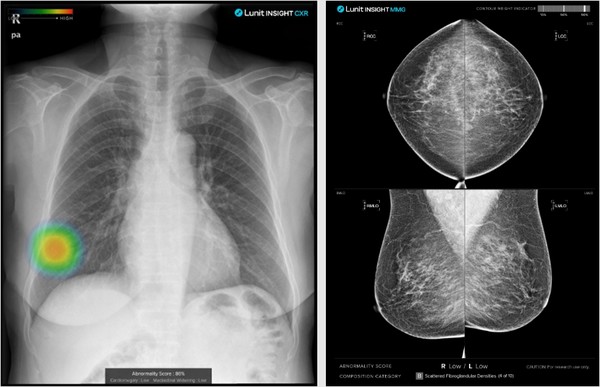

루닛의 암 진단 대표 AI는 '루닛 인사이트 CXR(흉부 X-ray)'와 '루닛 인사이트 MMG(유방조영술)' 등이다. 의료진의 진단을 돕는 '진단보조 소프트웨어'로 식품의약품안전처 품목허가를 획득한 제품이다.

현재 비즈니스 모델은 △하드웨어 결합형 SW 판매 △PACS 통합형 SW다. 의료영상 저장과 판독은 일반적으로 ▷촬영 ▷PASC저장 ▷판독 순으로 이뤄지는데, 촬영기기(하드웨어)에 내장된 SW를 통해 촬영 단계에서 작용하는 AI와 PACS와 통합으로 판독실에서 진단을 보조하는 AI 등으로 구성된다.

GE 헬스케어, 후지필름, 필립스 등 영상진단기기 기업들과 파트너십을 통해 기기 내장형 SW를 판매(기기별 수익)하고 있으며, PASC에 SW와 AI를 통합한 이미지당 결제 등 비즈니스모델을 구축하고 있다. 회사에 따르면 현재 HW 결합형 AI 판매는 연간 8만건 수준이며 이미지 해석은 연간 17억 건 수준이다.